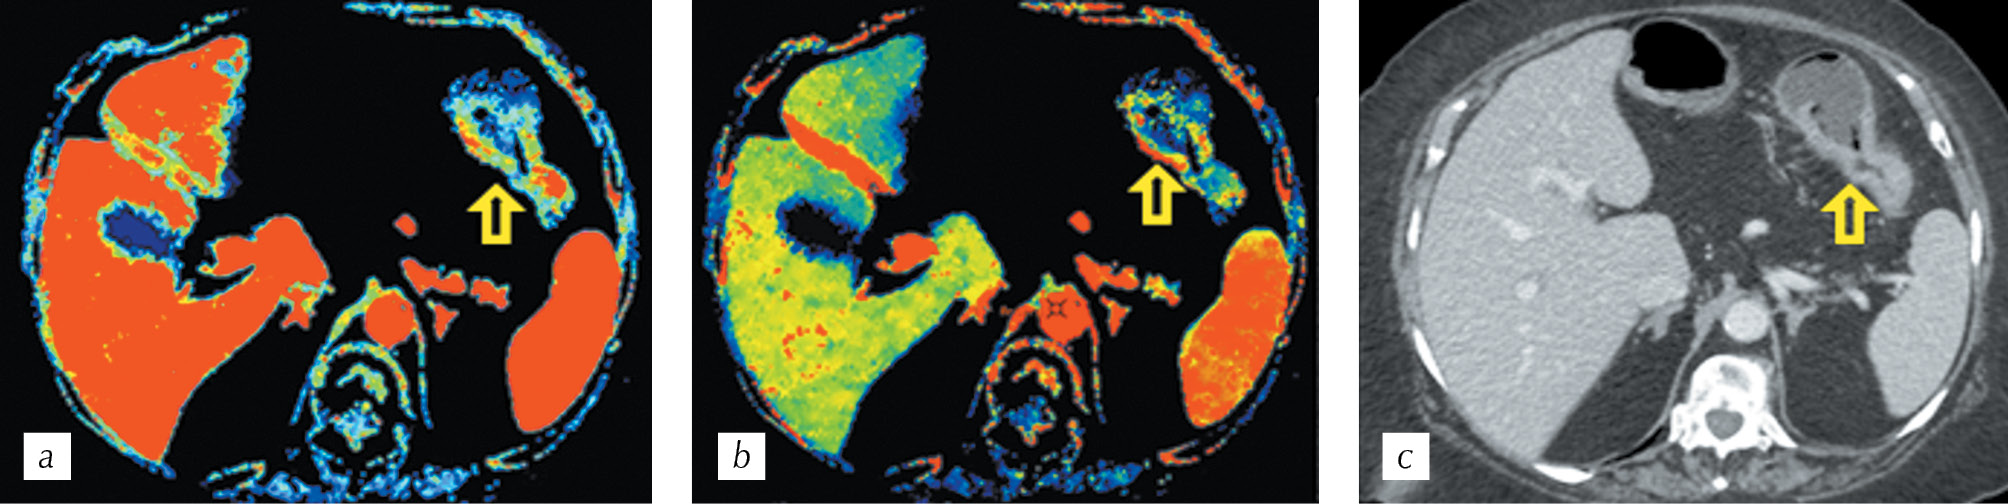

The abnormal vascularization of the tumor, in contrast to the adjacent intact walls of the intestine and colitis, was determined at the stage of visual assessment of parametric cards, despite the slight thickening of the intestinal walls (Fig. 4).

Fig. 4. CT perfusion (a, b). Parametric maps: a — volume and b — blood flow showing pathological increased blood flow in the descending colon tumor (arrows); c — HCT. Multiplanar reconstruction in the axial plane in the portal phase of scanning

Рис. 4. Перфузионная компьютерная томография (a, b). Цветные параметрические карты: а — объема и b — скорости кровотока, демонстрирующие патологический повышенный кровоток в стенках стенозирующей опухоли селезеночного изгиба ободочной кишки (стрелки); с — спиральная компьютерная томография. Мультипланарная реконструкция в аксиальной плоскости в портальную фазу сканирования